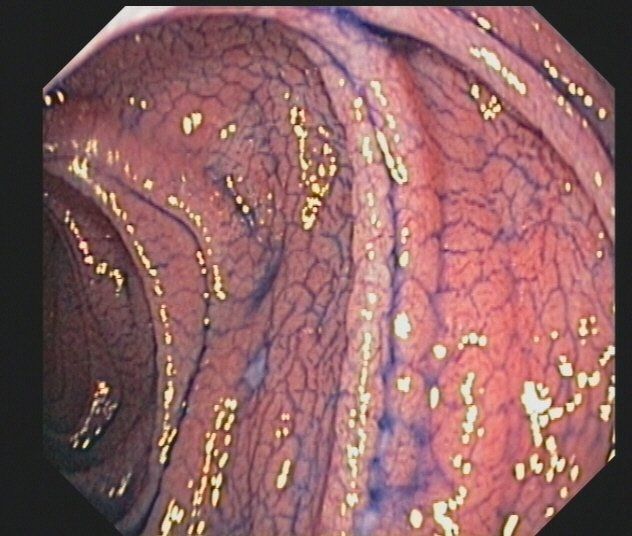

• Spezialsprechstunde für Patienten mit chronisch entzündlichen Darmerkrankungen Morbus Crohn und Colitis ulcerosa

• Barrett-Ösophagus

Zu den Untersuchungen gehört das Austasten des Mastdarms mit dem Finger und der fäkale Okkultbluttest, die ab dem 50. Lebensjahr empfohlen werden. Diese Maßnahmen ersetzen aber nicht die vollständige Darmspiegelung, mit der der gesamte Dickdarm inspiziert wird. So kann Darmkrebs frühzeitig erkannt werden, die Prognose wird verbessert. Durch Abtragung von Polypen, die Krebsvorstufen darstellen, wird die Entstehung von Darmkrebs verhindert. Die Entfernung von Polypen ist im Rahmen der Darmspiegelung meist problemlos und mit nur geringem Risiko möglich. Große Untersuchungen haben gezeigt, dass die Vorsorgekoloskopie sehr sicher ist.

Bei erblicher Prädisposition (Verwandte ersten Grades von Darmkrebs-Patienten) wird die Darmspiegelung früher durchgeführt. Patienten mit Polyposis-Syndromen (familiäre adenomatöse Polyposis, Peutz Jeghers Syndrom etc.), nicht polypösem Kolonkarzinom-Syndrom (HNPCC) und chronisch-entzündlichen Darmerkrankungen (vor allem Colitis ulcerosa) haben ein stark erhöhtes Darmkrebsrisiko und müssen sorgfältig endoskopisch überwacht werden. Die Leitlinien der Deutschen Gesellschaft für Verdauungs- und Stoffwechselerkrankungen (www.DGVS.de) geben die Untersuchungsintervalle vor.